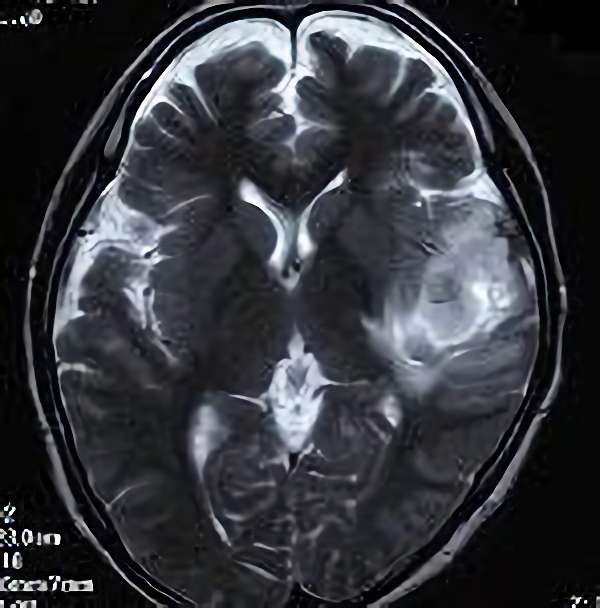

No.359 モニタリング

No.359 手術前

No.359 手術中

No.359 手術後

出血既往があり。2回の手術前血管内手術の後に、

Lateral transpeduncular approachにより再々出血予防を目的に

摘出手術を行う。完全摘出であることを確認した。

手術による合併症や後遺症なしで退院した。経過良好。